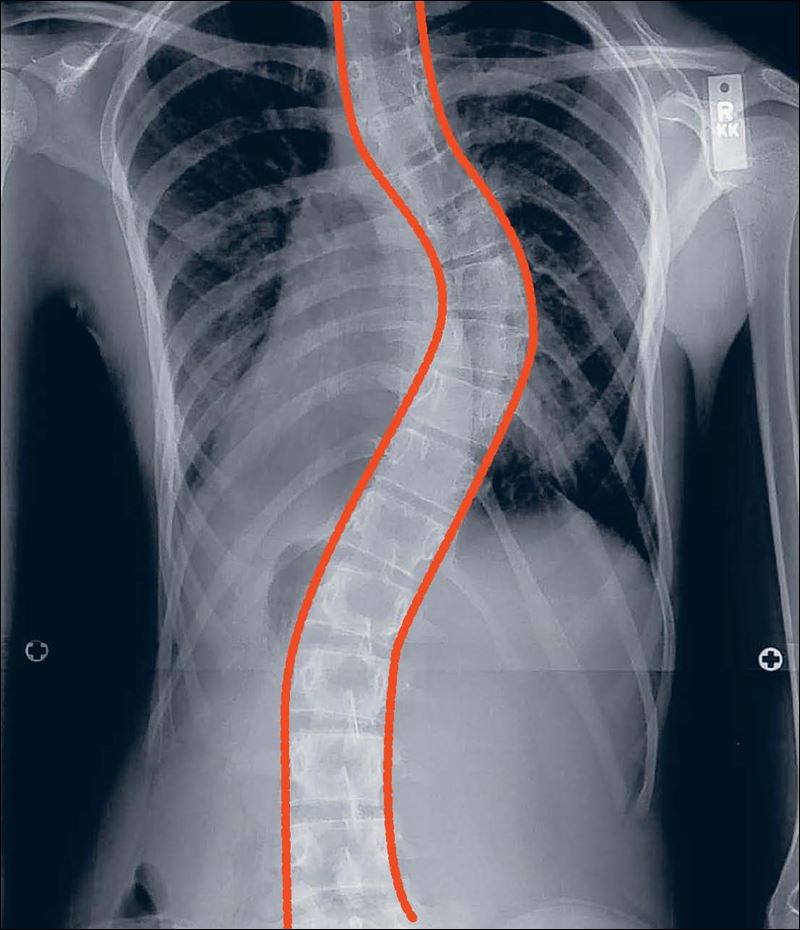

Essa formação de gibosidade vertebral na região torácica, também conhecida como corcunda, é chamada Escoliose, uma deformação morfológica nos três planos do espaço, torcendo a coluna para os lados, para frente, para trás e em torno do próprio eixo. A gravidade e a maneira como deverá ser tratada a escoliose é determinada através do grau de torção.

A deformação pode ser classificada como curva simples, com torção à direita ou à esquerda (escoliose em C); ou curva dupla (escoliose em S), podendo ainda ser identificada devido à região em que se encontra: cervicotorácicas, torácicas, toracolombares, lombares ou lombossacrais.

As principais causas da escoliose são idiopáticas, neuromusculares, a poliomielite, origem congênita e pós-traumática. Testes clínicos e radiografias, de maneira precoce, são muito importantes para o diagnóstico da doença.